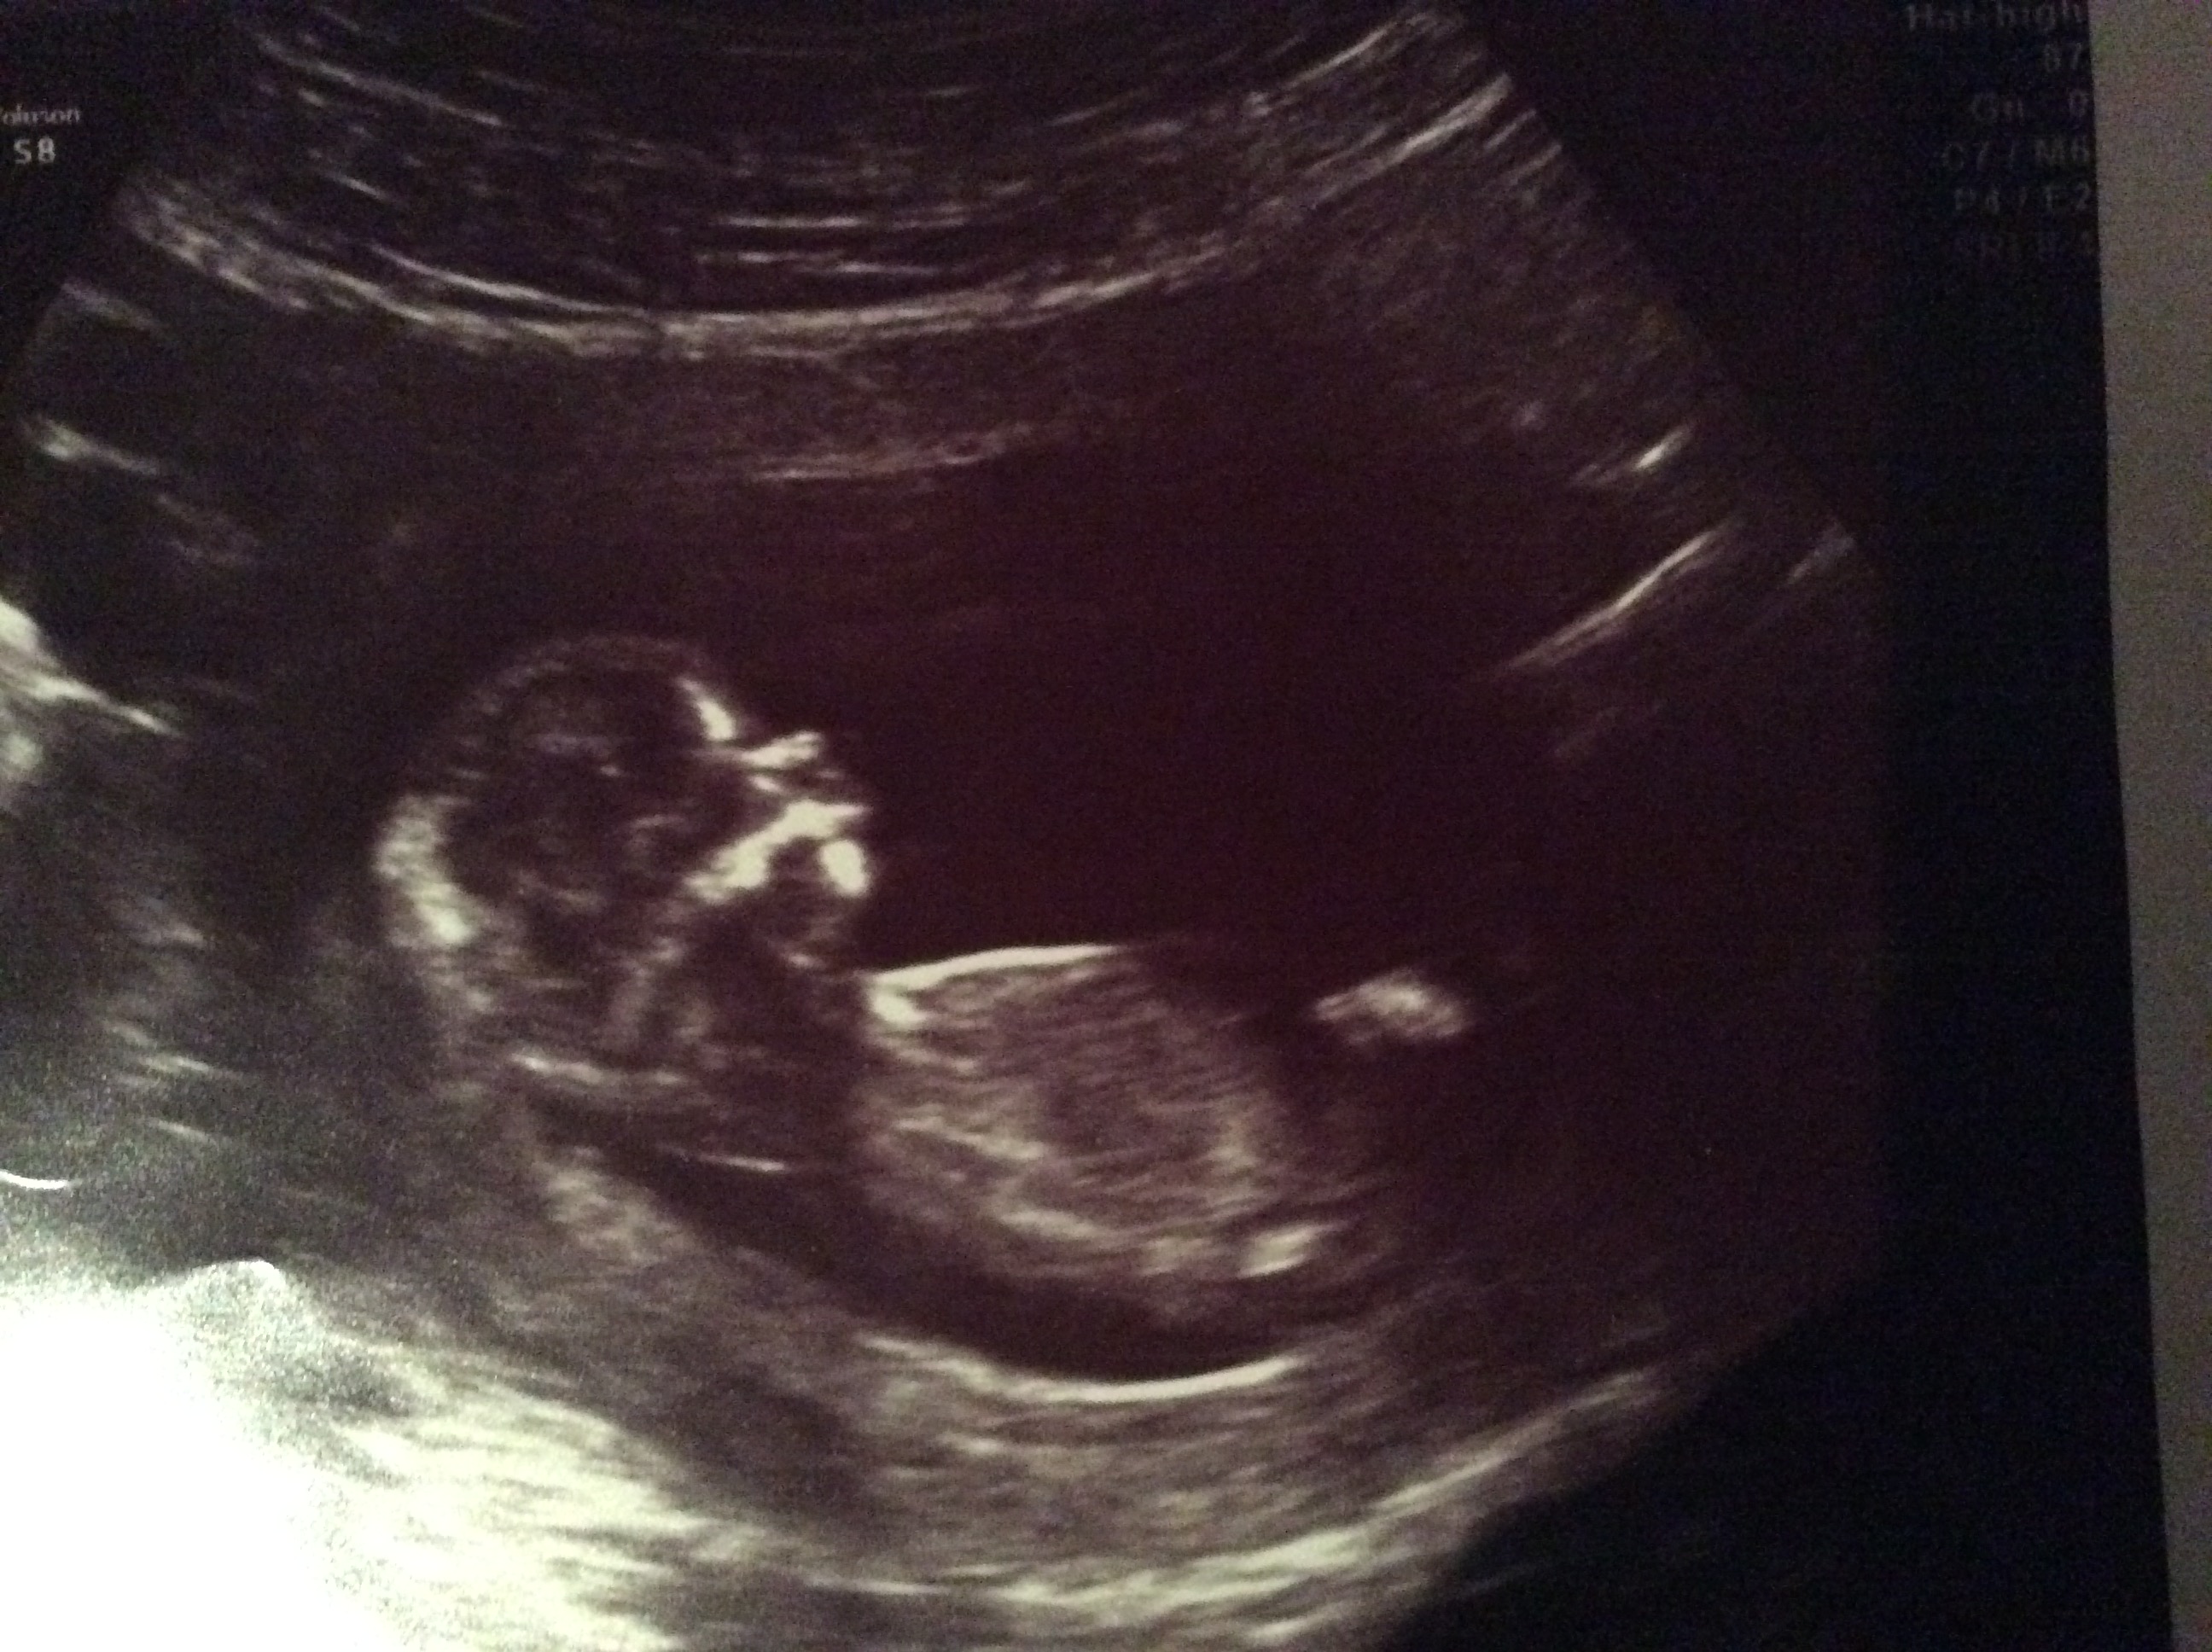

Skull theory any guesses desperate to know

Attachment 28505

Attachment 28506